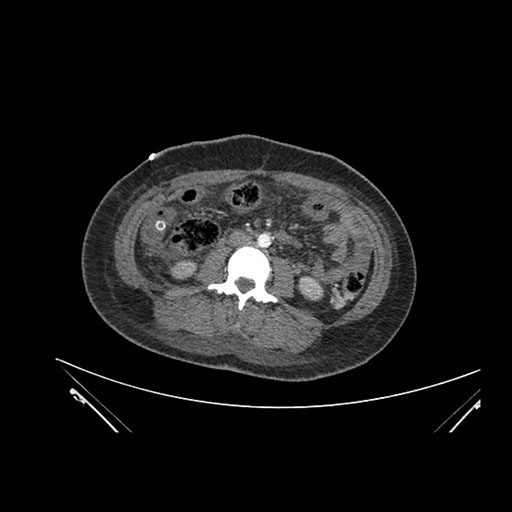

Axial Arterial